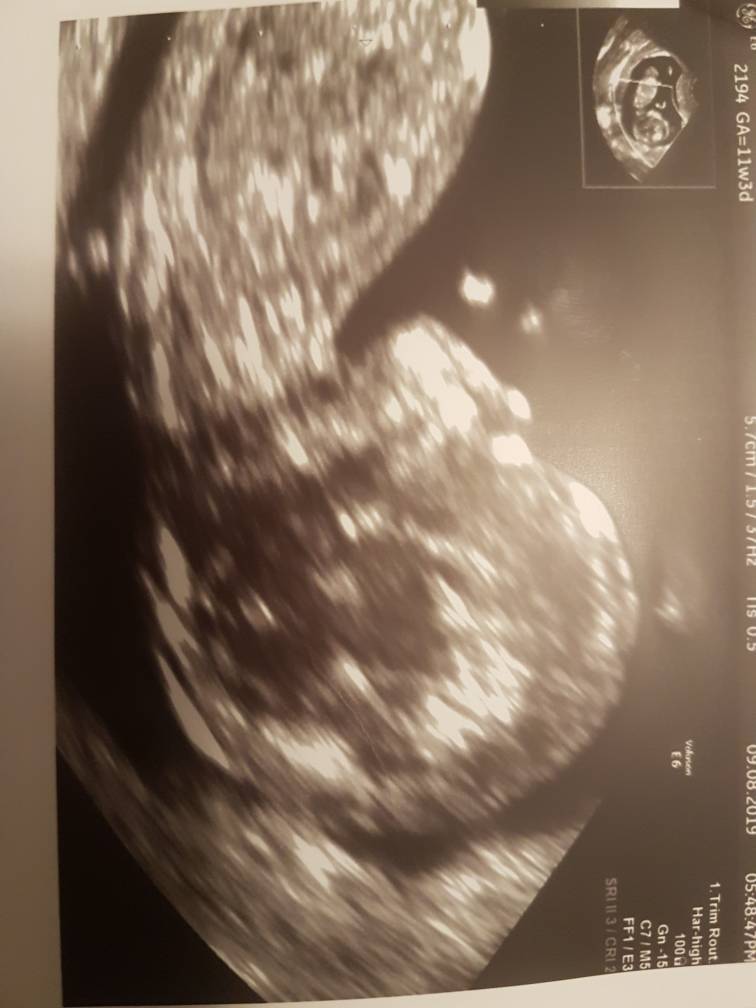

Wszystko ok, ryzyka niskie, kosc nosowa jest, przeziernosc 1.4.

Serducho bije 170/min.

Ale takie uparte dziecie... nie dosc ze przez mega tylozgiecie musialam miec badanie przezpochwowe to lekarka tak nawalala tym dzyngsem od usg zeby sie dziecko obrocilo a ono nic. A ja sie czulam zgwałcona

Musialam spacerowac, pic cole i dalej nic. W koncu sie na nanosekunde obrocilo zeby zlapac przeziernosc.